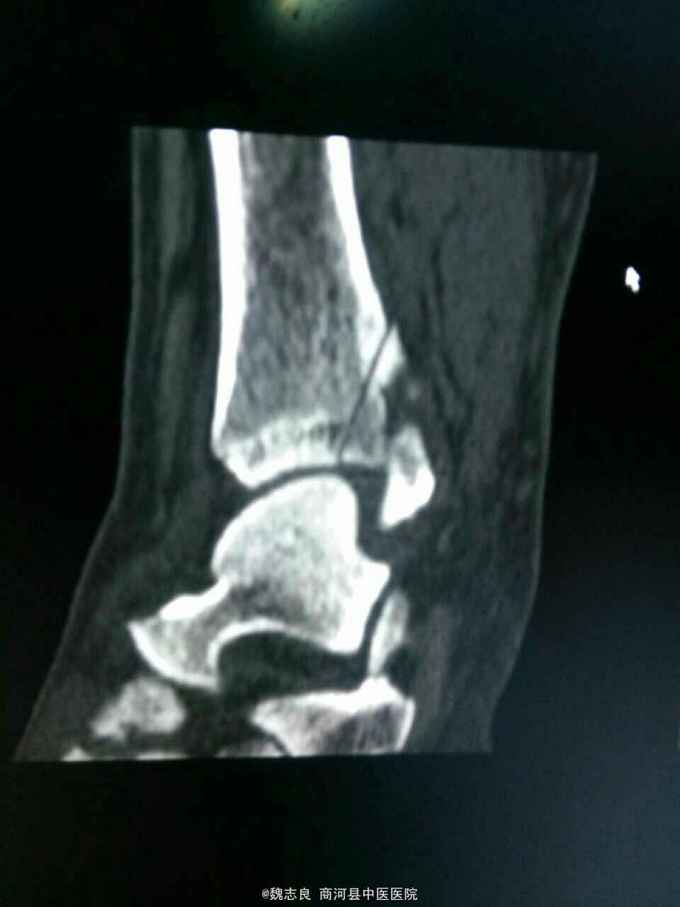

X线表现:正位像未见骨折征象,侧位像左外踝骨折。CT证实为内踝骨折。提醒我们关节内的骨折以及高度怀疑骨折的患者应该做ct检查,避免漏诊。